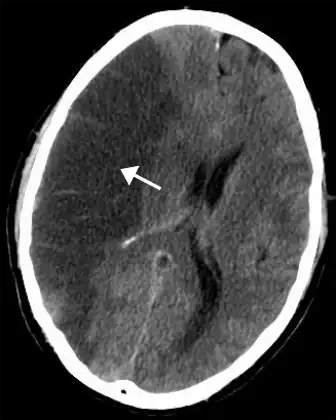

Silent stroke is stroke that does not have any outward symptoms, and people are typically unaware they had experienced stroke. Despite not causing identifiable symptoms, silent stroke still damages the brain and places the person at increased risk for both transient ischemic attack and major stroke in the future. Conversely, those who have had major stroke are also at risk of having silent stroke.[54] In a broad study in 1998, more than 11 million people were estimated to have experienced stroke in the United States. Approximately 770,000 of these were symptomatic and 11 million were first-ever silent MRI infarcts or hemorrhages. Silent stroke typically causes lesions which are detected via the use of neuroimaging such as MRI. Silent stroke is estimated to occur at five times the rate of symptomatic stroke.[55][56] The risk of silent stroke increases with age, but they may also affect younger adults and children, especially those with acute anemia.[55][57]

Stroke is diagnosed through several techniques: a neurological examination (such as the NIHSS), CT scans (most often without contrast enhancements) or MRI scans, Doppler ultrasound, and arteriography. The diagnosis of stroke itself is clinical, with assistance from the imaging techniques. Imaging techniques also assist in determining the subtypes and cause of stroke. There is yet no commonly used blood test for the stroke diagnosis itself, though blood tests may be of help in finding out the likely cause of stroke.[68] In deceased people, an autopsy of stroke may help establishing the time between stroke onset and death.

Imaging

For diagnosing ischemic (blockage) stroke in the emergency setting:[69]

- CT scans (without contrast enhancements)

- sensitivity= 16% (less than 10% within first 3 hours of symptom onset)

- specificity= 96%

- MRI scan

- sensitivity= 83%

- specificity= 98%

CT scans may not detect ischemic stroke, especially if it is small, of recent onset,[10] or in the brainstem or cerebellum areas (posterior circulation infarct). MRI is better at detecting a posterior circulation infarct with diffusion-weighted imaging.[71] A CT scan is used more to rule out certain stroke mimics and detect bleeding.[10] The presence of leptomeningeal collateral circulation in the brain is associated with better clinical outcomes after recanalization treatment.[72] Cerebrovascular reserve capacity is another factor that affects stroke outcome – it is the amount of increase in cerebral blood flow after a purposeful stimulation of blood flow by the physician, such as by giving inhaled carbon dioxide or intravenous acetazolamide. The increase in blood flow can be measured by PET scan or transcranial doppler sonography.[73] However, in people with obstruction of the internal carotid artery of one side, the presence of leptomeningeal collateral circulation is associated with reduced cerebral reserve capacity.[74]